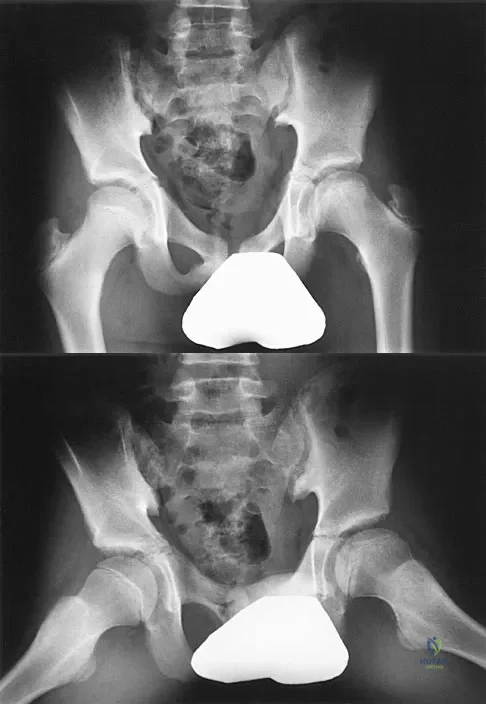

The parents of a 13-year-old boy with Down syndrome report that he has an increasing limp and decreased endurance with activities. Lateral flexion-extension radiographs of the cervical spine show no evidence of instability. Examination reveals a right Trendelenburg limp and an obvious limb-length discrepancy. Hip motion is symmetric except for some decreased abduction on the right side. A standing AP radiograph is shown in Figure 20. Management should consist of

Explanation

A 22-year-old man has mild hip pain bilaterally and multiple skeletal lesions. Based on the pelvic radiograph shown in Figure 30, what is the inheritance pattern for his disorder?

Explanation